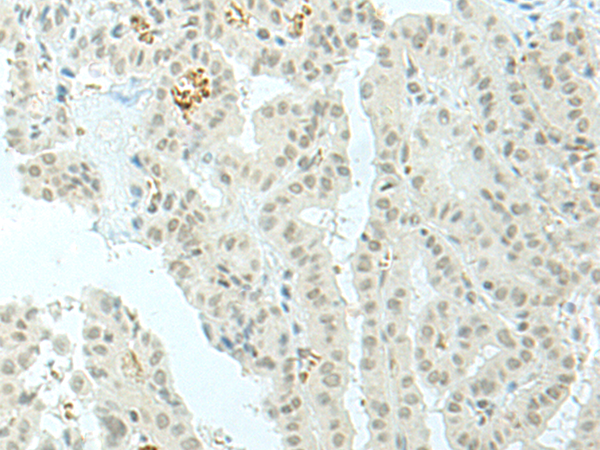

分类: 科研抗体货号: P06466别名: RBM35B应用: WB,IHC反应种属: Human, Mouse, Rat